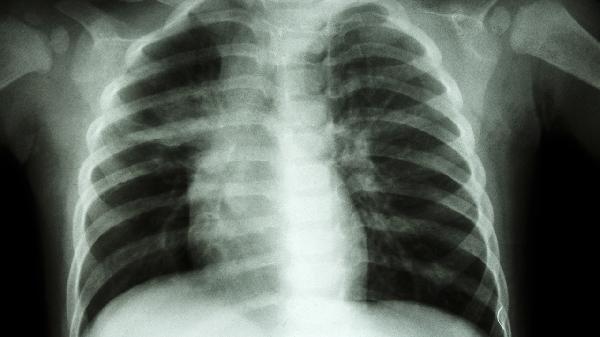

右肺尖磨玻璃結(jié)節(jié)可能由感染性病變、非感染性炎癥、早期肺癌等因素引起,可通過抗感染治療、手術(shù)切除等方式干預(yù)。磨玻璃結(jié)節(jié)是指CT影像中呈現(xiàn)半透明云霧狀陰影的肺內(nèi)病灶,需結(jié)合動態(tài)隨訪與病理檢查明確性質(zhì)。

非典型腺瘤樣增生或原位腺癌在影像學(xué)上可呈現(xiàn)純磨玻璃結(jié)節(jié),通常無典型癥狀。需通過CT隨訪觀察結(jié)節(jié)增長速率、實性成分變化,必要時行胸腔鏡下肺段切除術(shù)。病理確診后根據(jù)分期選擇靶向治療。